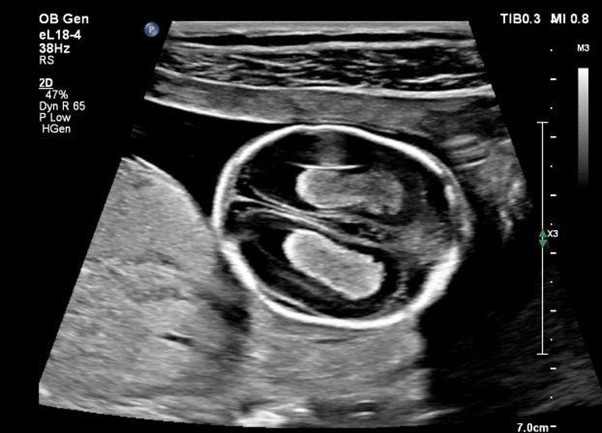

Для безопасности все современные УЗ-аппараты обязаны отображать на экране тепловой индекс — TI. Это оценка максимально возможного повышения температуры ткани в градусах Цельсия, если бы исследование проводилось при текущих настройках мощности и времени.

Индекс TI бывает трех типов, в зависимости от сканируемой ткани, поскольку каждая имеет разное поглощение и кровоснабжение:

- TIS (Soft Tissue Thermal Index): индекс для мягких тканей, например печени и почек.

- TIB (Bone Thermal Index): индекс для сканирования вблизи кости (актуально в поздние сроки беременности, когда луч проходит через кость плода).

- TIC (Cranial Thermal Index): индекс для сканирования через кость черепа при нейросонографии.

Врач должен строго соблюдать пороговые значения.

- При рутинном 2D-сканировании рекомендуется поддерживать TI ≤ 1,0.

- В акушерстве при обследованиях в первом триместре крайне нежелательно превышать TI = 0,7, а также нужно минимизировать время экспозиции.

- Все импульсные доплеровские режимы (PW, Color Doppler) имеют значительно более высокие значения TI, чем 2D-режимы, так как работают с более длительными и мощными импульсами. При использовании доплера всегда требуется сокращать время экспозиции до абсолютного минимума.